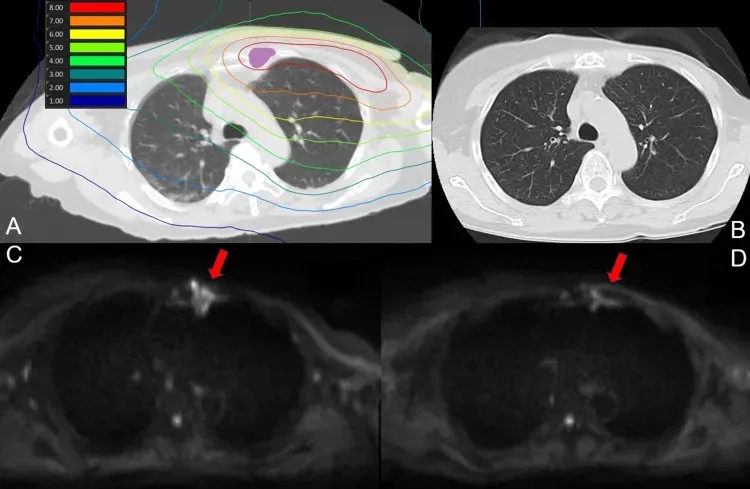

《Cureus》报道了全球首个采用基于加速器的BNCT系统,治疗放疗后复发性乳腺癌的临床研究,结果显示:所有病例90天内均未出现3级及以上不良反应。其中一位72岁女性,既往曾因左侧乳腺癌先接受化疗,后行乳房切除术(ypT2N1M0);后续左侧胸骨旁淋巴结复发,接受激素治疗与化疗,4年前左胸壁及胸骨旁区域接受30次照射。因左侧内乳淋巴结复发接受BNCT治疗。

结果显示:BNCT后1天、7天MRI检查及30天、90天CT扫描,均未显示放射性肺炎迹象。下图1为肺部剂量分布及治疗后90天CT、MRI扫描。

▲图源“Cureus”,版权归原作者所有,如无意中侵犯了知识产权,请联系我们删除